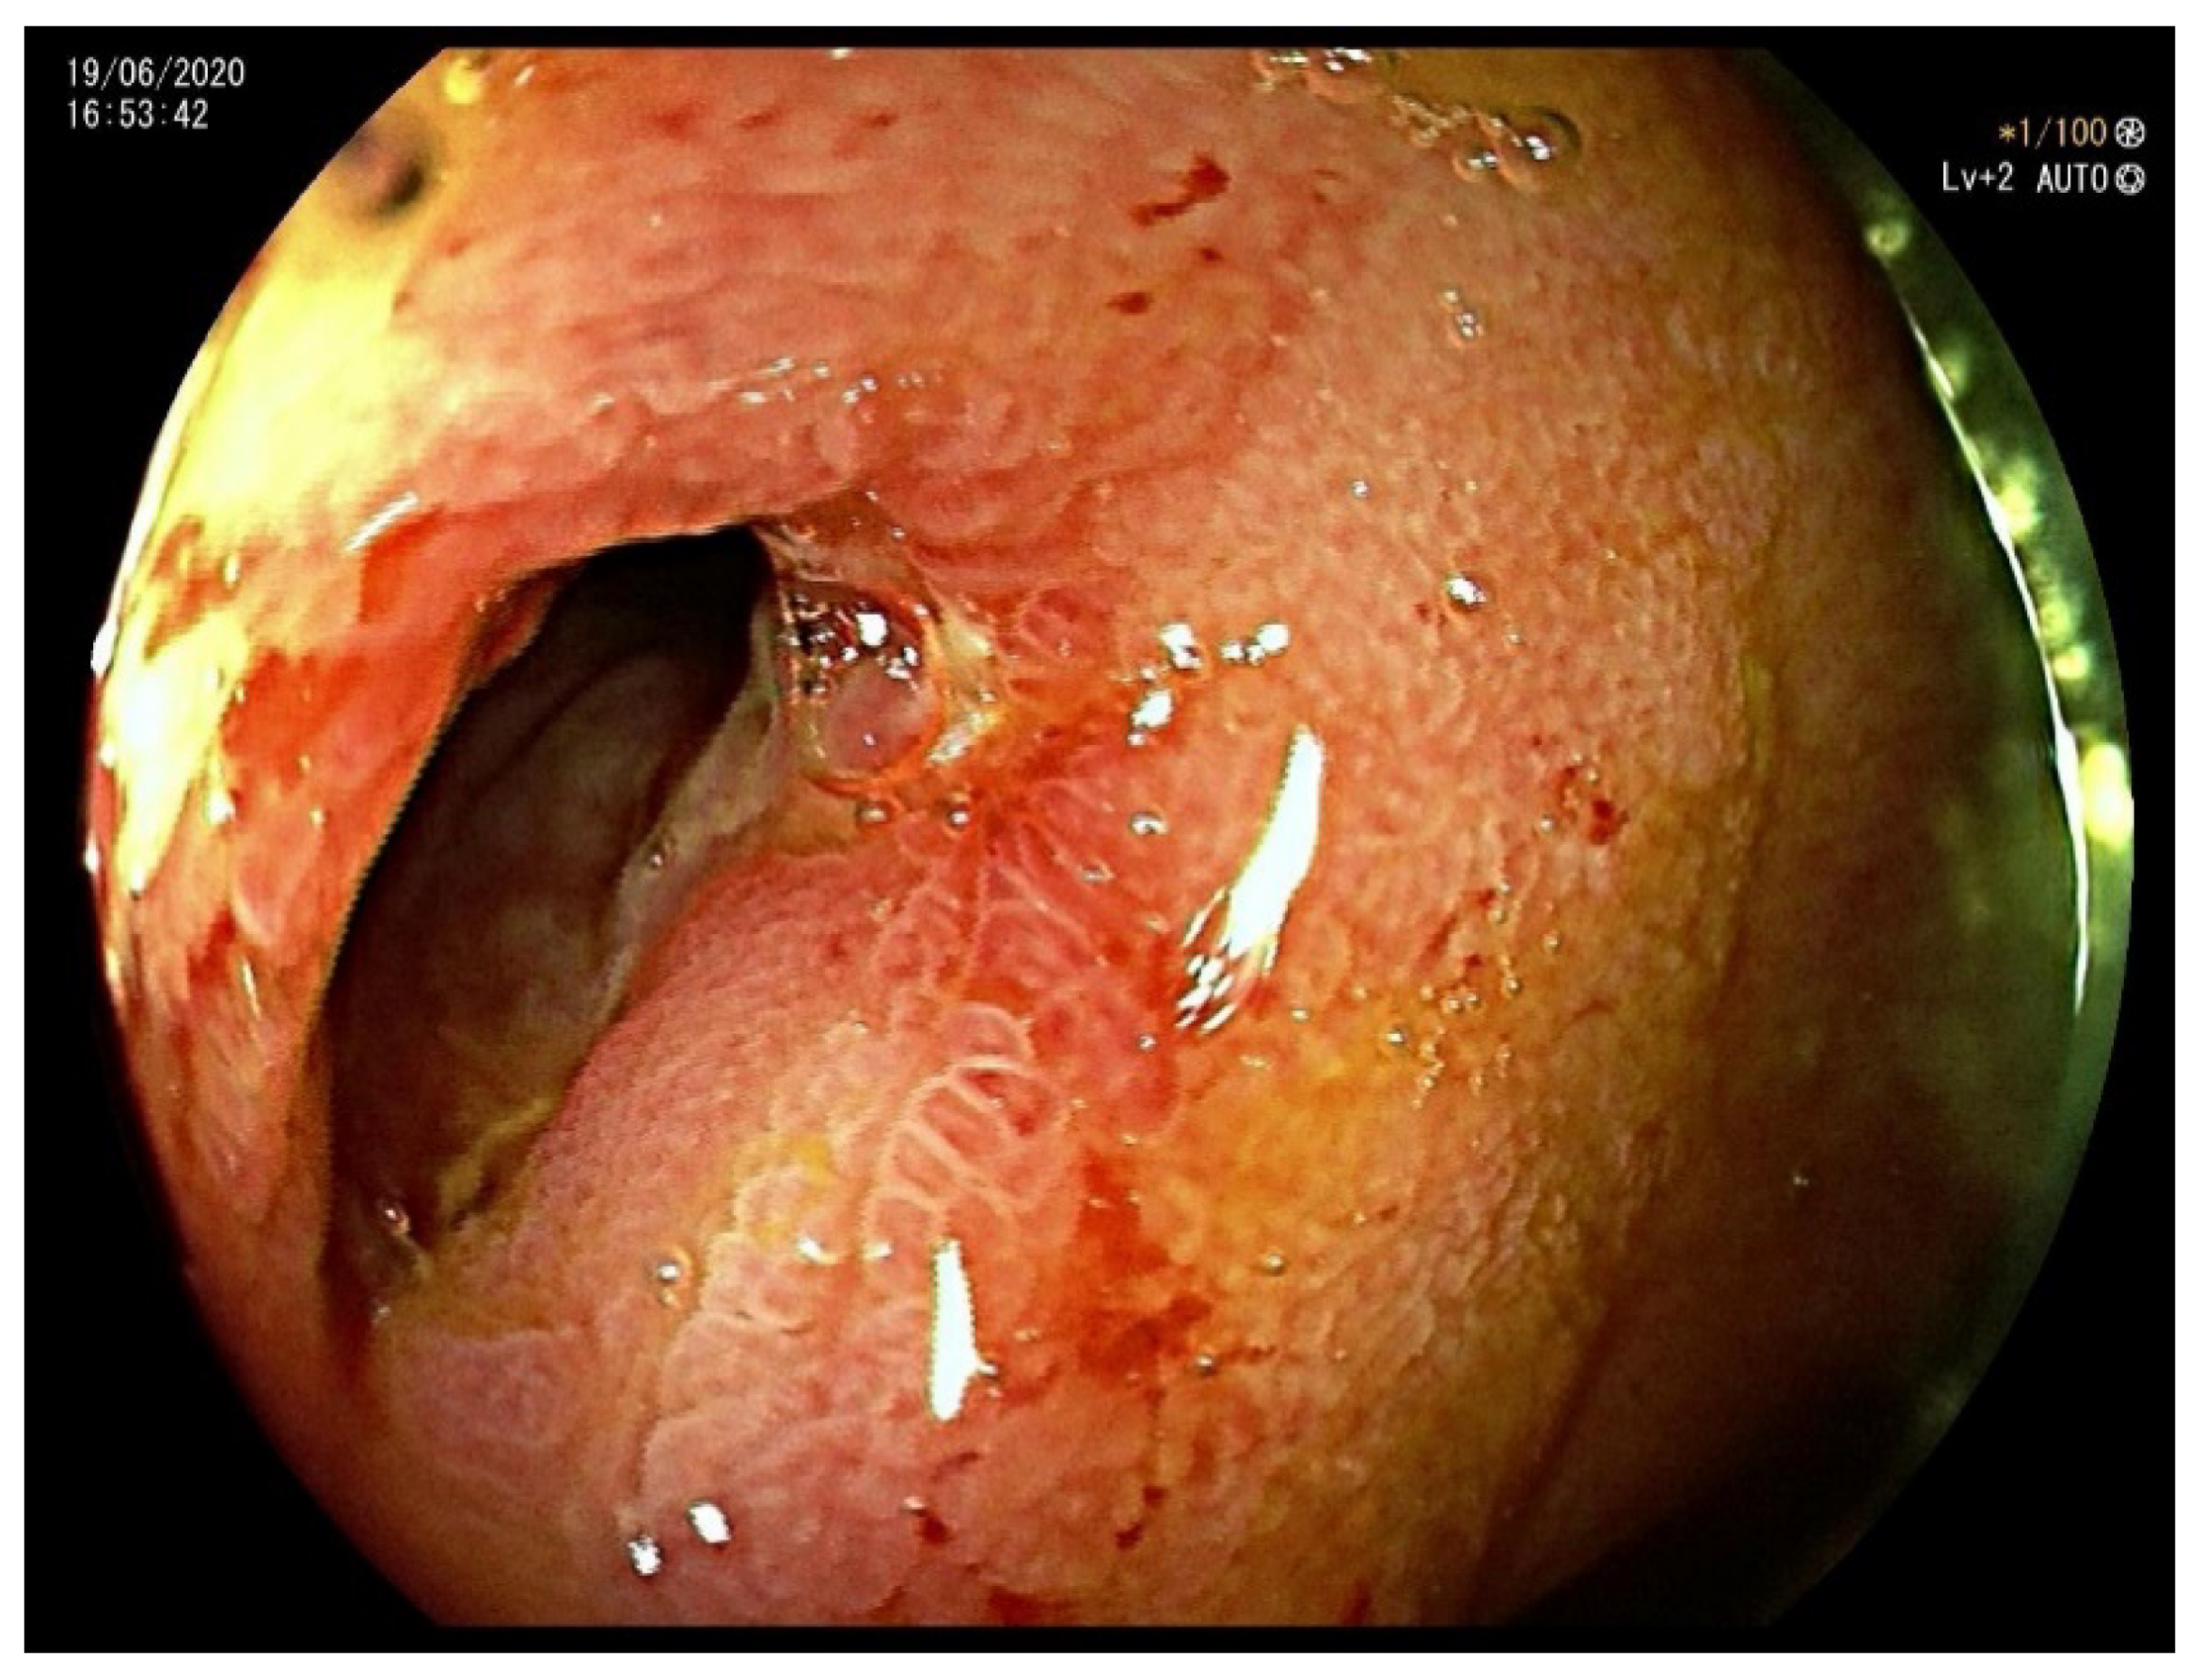

Figure 2.

Colonoscopy showing a stenosis of the ileocecal valve suspicious for inflammatory bowel disease.

On clinical examination, the abdomen was tender all over the quadrants, without any peritoneal signs elicited by manual palpation. Laboratory tests showed an increased white blood cell count of 12,000/mm3 and a C-reactive protein of 14.2 mg/dL. Computed tomography scan showed thickening of the terminal ileum with a 14 mm intraluminal radiopaque mass causing small bowel obstruction (Figure 1). Decision was taken to perform laparoscopic exploration of the abdomen for diagnostic and therapeutic purposes. During the laparoscopy, the thickened segment of small bowel was opened and a foreign body resembling a fruit pit was found within the inflamed lumen. The foreign body was extracted and closure of the small bowel was performed. Upon questioning the patient, after surgery, about the possibility of foreign body ingestion, it was discovered that the patient had accidentally swallowed a medlar pit a couple of days earlier. A month later a colonoscopy was performed, which confirmed a stenosis of the ileocecal valve suspicious for inflammatory bowel disease (Figure 2). Pathology examination of the biopsy specimens confirmed the diagnosis of CD involving the terminal ileum and the ileocecal valve. Due to the nature of the stenosis, which was fibrotic and stenotic, an ileocecal resection was planned and performed successively without any complications.